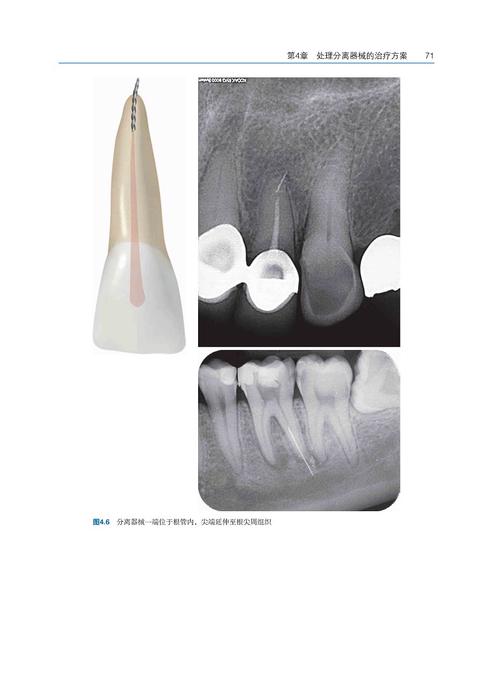

- 影像学定位:

- X线近远中+颊舌向投照(确定三维位置)

- CBCT精准定位(距根尖距离、偏中心角度)

- 分离器械位置(冠1/3 vs 根尖1/3)

- 根管通畅度(锉能否通过分离点)